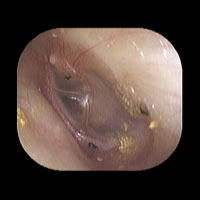

右急性中耳炎(中等症)

鼓膜がやや赤くなっています。鼓膜の奥に膿が透けて見えています。鼓膜の腫れはありません。抗生剤の内服で鼓膜切開を行わずに16日目で治りました。

初診日

7日目

14日目

16日目